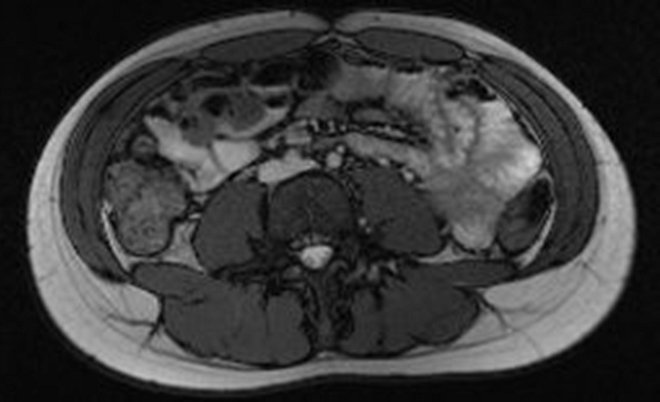

MR břicha (obr. 1, 2, 3, 4, 5):

/ Obr. č. 1: MR břicha /

/ Obr. č. 2: MR břicha /

/ Obr. č. 3: MR břicha /

/ Obr. č. 4: MR břicha /

NÁLEZ: ledviny normálního tvaru, velikosti a uložení, kontury ostré, KPS štíhlé.

/ Obr. č. 5: MR břicha /

V pravé ledvině patrné četné pruhovité okrsky restrikce difuze přes celou šíři parenchymu, vlevo normální nález bez restrikce

difuze.

ZÁVĚR: známky pyelonefritis ac. l.dx.